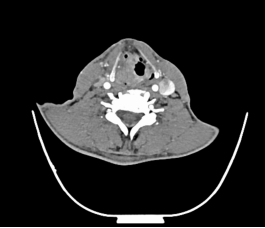

颈部恶性肿瘤在颈部肿块中占据很大比重,而80%的颈部恶性肿瘤为转移性恶性肿瘤,而这些转移性恶性肿瘤中80%的原发部位为头颈部,常见的有鼻咽癌颈淋巴结转移、下咽癌颈淋巴结转移、喉癌颈淋巴结转移,接下来我们来一一看看。

下咽部淋巴组织丰富,较易发生淋巴结转移,早期常转移至同侧颈动脉三角区颈深部淋巴结,多为分化程度较差的癌。而且由于下咽部位置隐蔽,常常原发灶不易发现,还有转移灶很大,原发灶很小的情况。

常见的还有口咽、口腔、鼻腔鼻窦癌颈淋巴结转移、甲状腺癌颈淋巴结转移等。颈部恶性肿瘤的诊断需要借助详细的病史、全面的体格检查及辅助检查(包括彩超、CT、电子鼻咽喉镜等),最重要的还是要去耳鼻咽喉头颈外科专科就诊。